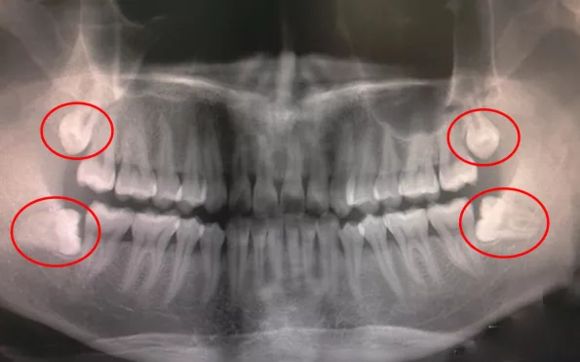

有4顆智齒的全景片

一般來說,智齒有幾顆,到醫院一拍全景片就可以看得很清楚,至於(yu) 要分為(wei) 幾次拔除,這個(ge) 根據**自己的意願來進行。